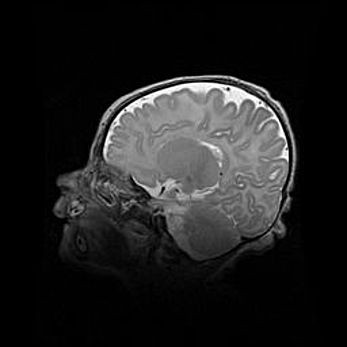

Аномалия Денди-Уокера. Признаки гипоплазии мозолистого тела.

Возраст: 5 месяцев 3 дня

Вес: 5550 г

Пол: мужской

Окружность головы: 39 см

Срок гестации: 40 недель

Аномалия Денди-Уокера – это порок развития головного мозга, для которого характерна триада симптомов: гипотрофия или аплазия червя мозжечка и/или полушарий мозжечка, расширение четвёртого желудочка с формированием ликворной кисты задней черепной ямки, гипертензионная гидроцефалия различной степени.

Гипоплазия мозолистого тела относится к дефектам внутриутробного этапа развития мозговой ткани, возникающим в процессе закладки структур головного мозга, что происходит на начальных этапах развития эмбриона.